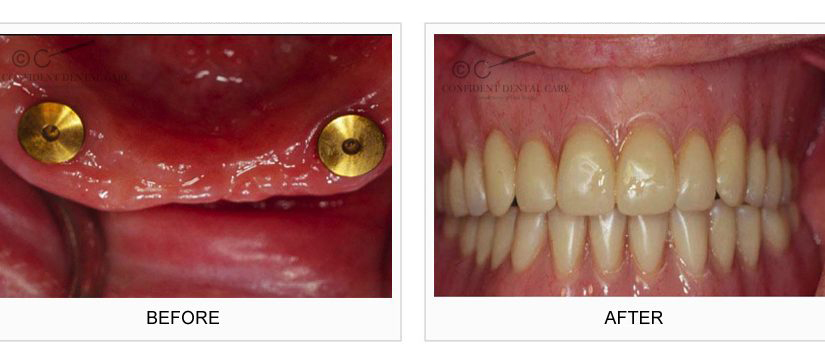

Implant Support Denture